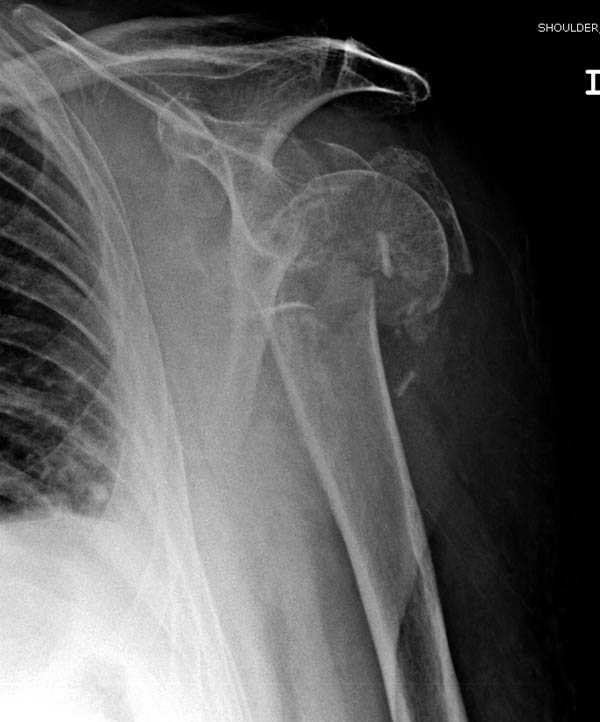

Здесь пример открытой репозиции 57 летнего с переломом плеча (1,2) смещение обнаружено на интероперационном снимке. При нормальной прямой проекция (3) угловое смещение обнаружили в аксиальной проекции (4)